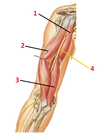

1? 2?

1: Supraspinatus muscle

2: Serratus anterior muscle